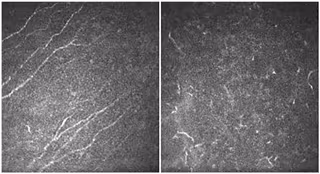

Córnea de un ojo sano (izquierda) y de un paciente con aniridia (derecha), mostrando cambios en las células defensivas del tejido que reflejan la alteración de la córnea.

Córnea de un ojo sano (izquierda) y de un paciente con aniridia (derecha), mostrando cambios en las células defensivas del tejido que reflejan la alteración de la córnea. - CSORBA ET AL, CURRENT EYE RESEARCH.